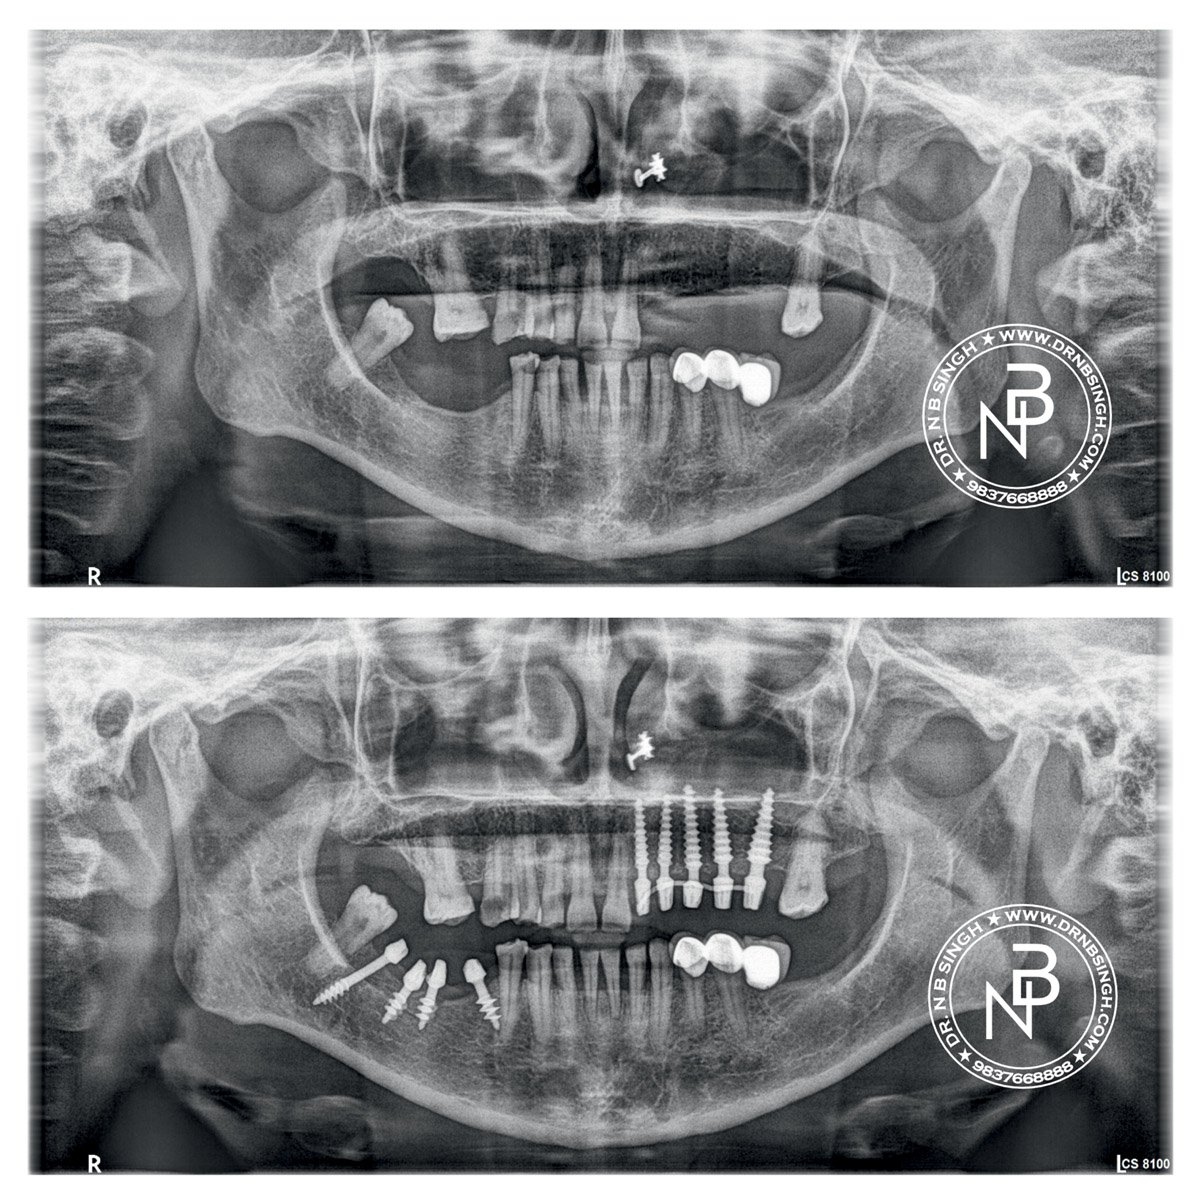

Case-10 Basal and compressive implants – segmental Restoration

Dr. N.B. Singh